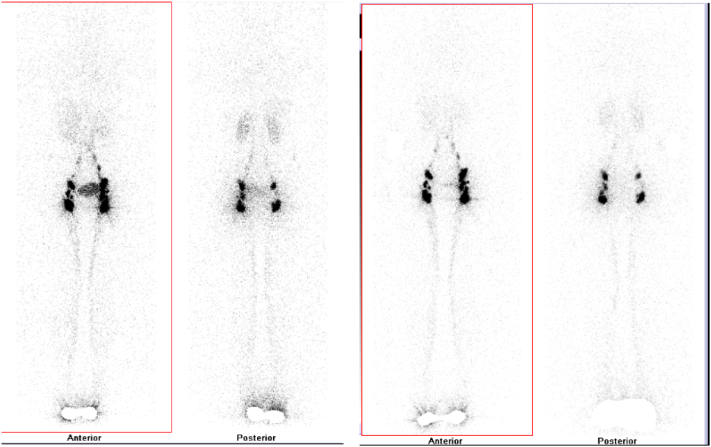

A 19-years-old female was presented to our polyclinic with a chief complaint of shortness of breath 1 year before admission. History of cough, fever, and chest pain were all denied. Her physical examinations were unremarkable. Further examination revealed an accumulation of fluid in the pericardial sac. Evaluation for autoimmune disease, tuberculosis, and malignancy all came back negative. The patient had undergone 3 pericardiocentesis procedures in the span of 1 year. Fluid with a milky white appearance was removed from the pericardial sac, a total of 1255 ml, 1180 ml, and 1000 ml at each tapping respectively. Pericardial fluid analysis revealed an increased level of triglyceride (1261 mg/dL), cholesterol (124.7 mg/dL), predominance of lymphocytes (97.2 %), and positive Sudan III staining. There were no bacteria found in the cytology and culture of the pericardial fluid. Lymphoscintigraphy showed the flow of radioactivity is stopped at the supradiaphragmatic level. There was no pathological activity in thoracic region and pericardium region. There is suspicion of lymphatic leakage or obstruction at the supradiaphragmatic level with no pericardial activity in the location of pericardial effusion (Fig. 1). The patient was diagnosed with recurrent primary chylopericardium. We highly encourage the patient to undergo surgery following recurrent accumulation of chyle in the pericardial sac however, the patient was hesitant to follow through.

Fig. 1.

Lymphoscintigraphy showed suspected leakage or obstruction of lymph at the supradiaphragmatic level.